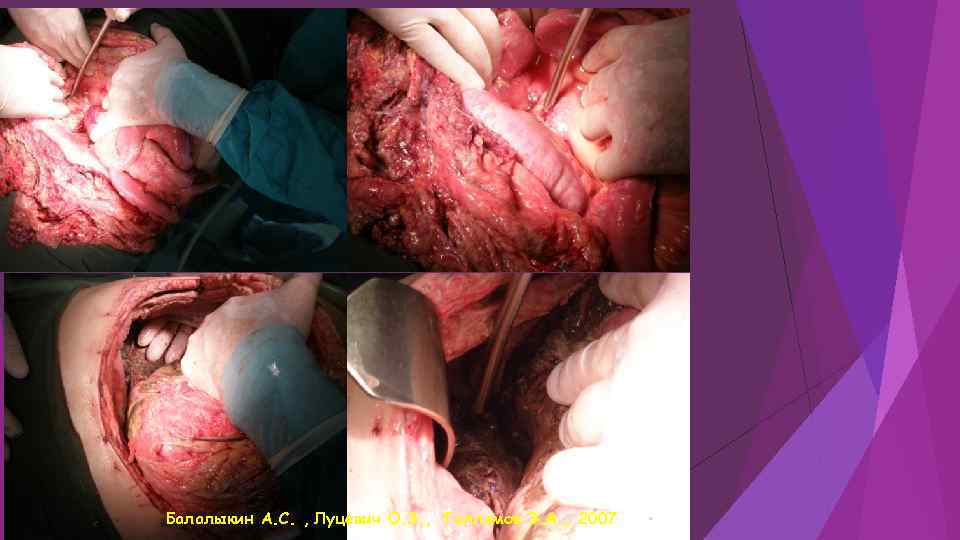

Балалыкин А. С. , Луцевич О. Э. , Галлямов Э. А. , 2007

Балалыкин А. С. , Луцевич О. Э. , Галлямов Э. А. , 2007

Этапная санация при распространенном деструктивном панкреонерозе Балалыкин А. С. , Луцевич О. Э. , Галлямов Э. А. , 2007

Этапная санация при распространенном деструктивном панкреонерозе Балалыкин А. С. , Луцевич О. Э. , Галлямов Э. А. , 2007

Этапная санация при распространенном деструктивном панкреонерозе Балалыкин А. С. , Луцевич О. Э. , Галлямов Э. А. , 2007

Этапная санация при распространенном деструктивном панкреонерозе Балалыкин А. С. , Луцевич О. Э. , Галлямов Э. А. , 2007